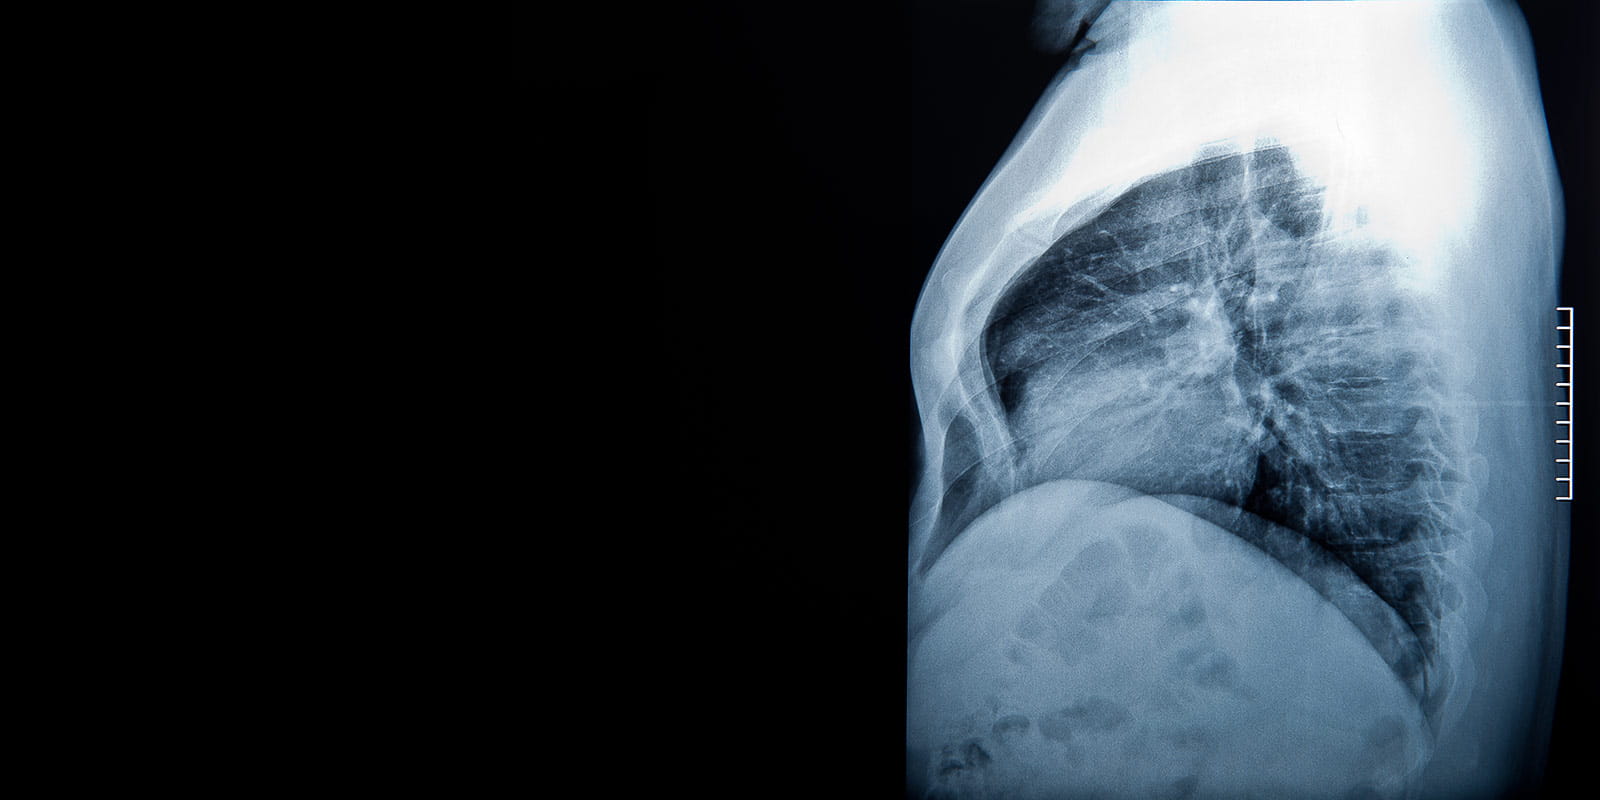

Expert Diagnosis and Treatment for Diseases of the Chest and Esophagus

Highly skilled surgeons in the Division of Thoracic and Esophageal Surgery at University Hospitals provide the latest therapies for conditions affecting the lungs and esophagus. The same surgeons perform procedures at multiple University Hospitals locations across the region, offering a full-service program for patients in surrounding communities.